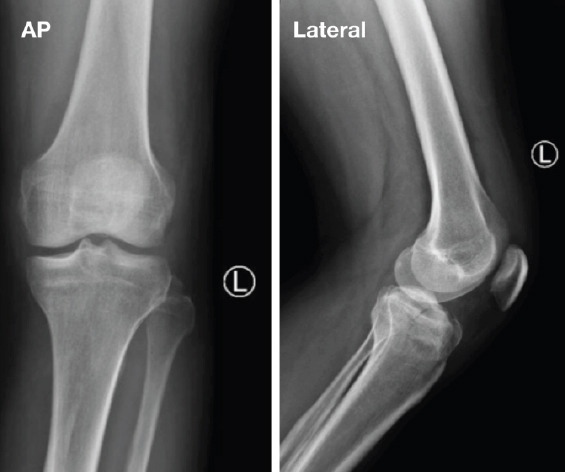

Case report: A 44-year-old medically free male sustained a hyperextension injury to his left knee after being kicked by a horse. Imaging showed an anteromedial tibial plateau rim fracture, as well as a fibular head fracture. Examination under anesthesia revealed a stable knee. Open reduction and internal fixation were conducted using a 3.5 locking compression plate L-shaped plate, and screws. Post-operative outcomes at 7 months of follow-up, the patients had complete knee mobility, no significant ligamentous damage, and returned to regular activities without discomfort.